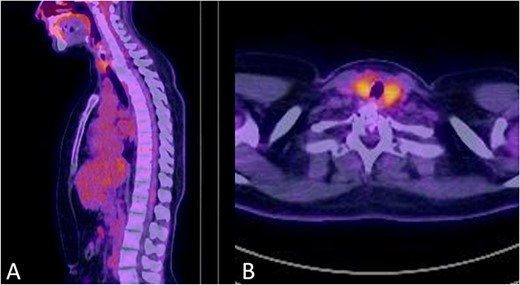

There were no surgical complications intraoperatively or postoperatively. A 3-day postoperative X-ray determined there was no mispositioning of the VBR and instrumentation (Fig. 3). There were no inpatient medical complications and pain was managed appropriately. Patient was discharged from hospital shortly after the operation and recovery. As outpatient, she did not complain of pain or wasn’t immobilized outside of the hospital. A 15-month follow-up MRI and 30-month follow up Positron emission tomography–computed tomography (PET-CT) maintained to show that the patient was tumour free (Figs 4 and 5). Lastly, upon assessment in clinic over 30 months, the patient was fully mobile and self-reported to be pain free, living independently and comfortably. There were no hardware related issues and there wasn’t any development of infection.

No signs of tumour recurrence at 30-months postoperative follow up PET-CT in July 2022.